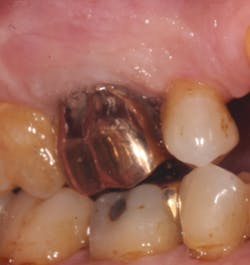

A 69-year-old male with a noncontributory medical history presented with 5 mm of recession, less than 1 mm of attached gingiva, and cervical notching on tooth No. 3. The tooth had an existing gold onlay and was caries-free (figures 1a and 1b). Radiographic analysis showed periodontal bone loss and a radiolucency at the apex of the tooth. The patient denied implant therapy and wanted to save the tooth.